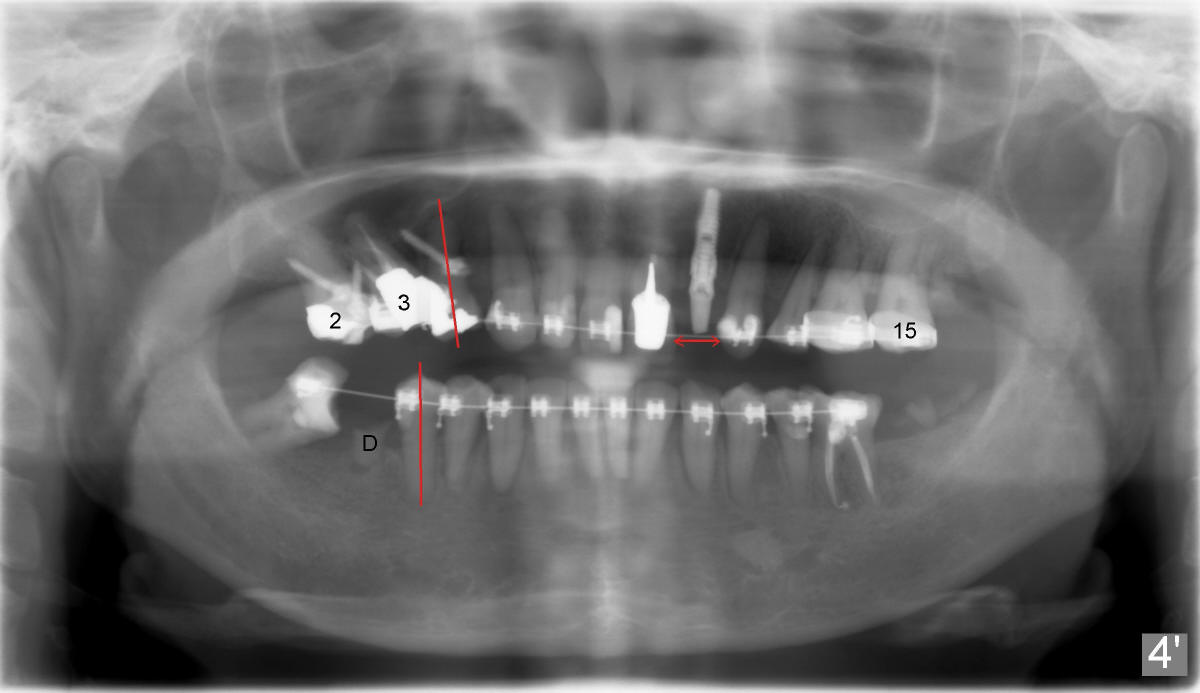

Fig.4': Eleven months of ortho: #29 is upright; the mesial root of #30 has been extracted; the distal root retains (D). The occlusal plane of the lower arch is flat, as compared to Fig.4. #2,3 are being intruded using 3 mini-implants; the axis of #4 has been improved. #15 appears to have been intruded. The space has been increased for #10 implant (arrows).